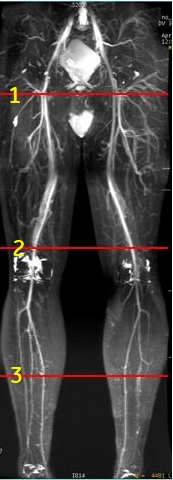

Figure 2. Localizer for slab position for 3-stations

Table 2. Image legend Number Description 1 Center of the slab for station 1 2 Center of the slab for station 2 3 Center of the slab for station 3